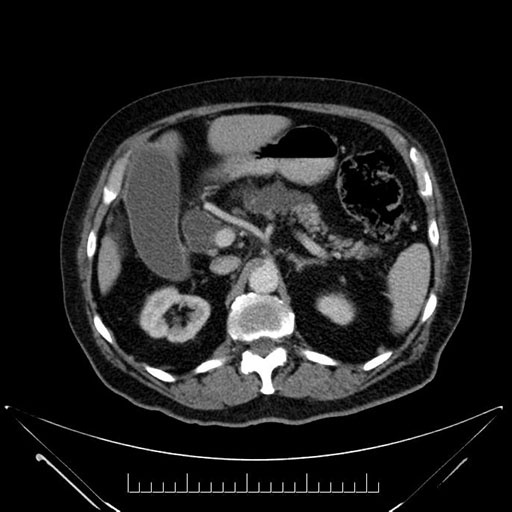

Coronal - stented